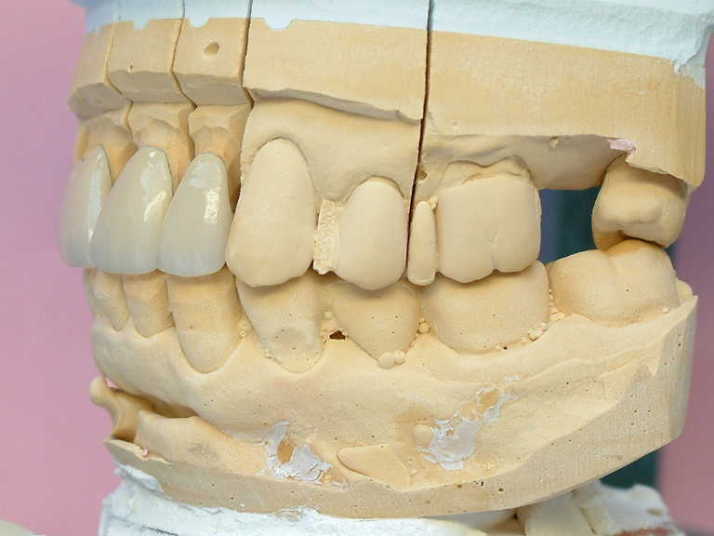

メタルコアー 個歯トレー&各個トレにて印象 |